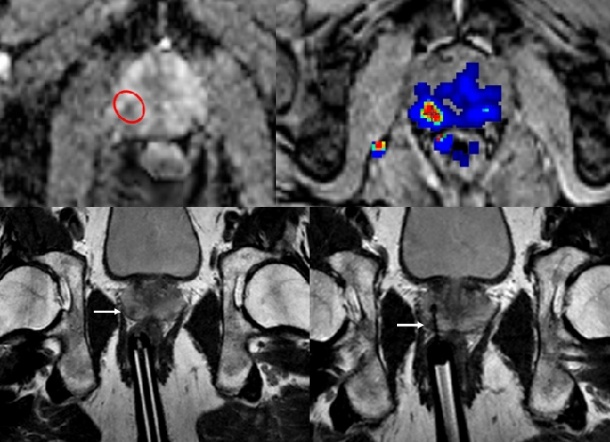

Diese Bilder dienen dann bei auffälligen Befunden als Grundlage (Back-up) für eine stereotaktische, dreidimensionale, MR-gestützte Biopsie. Durch die MR-Kontrolle während der Biopsie kann die Gewebeverformung in der Prostata – im Gegensatz zur Bildfusion – unter Echtzeitbedingungen ermittelt werden. Die Diffusionsbildgebung ermöglicht während der Biopsie die Identifikation potenziell klinisch relevanter Tumoren, da die Veränderung des Gewebes in der Diffusionswichtung mit dem Gleason-Score korreliert. Dieses Vorgehen erlaubt eine äußerst sparsame Gewebsentnahme – oft reicht eine einzige Probenentnahme aus – was das Infektionsrisiko bei transrektalen Biopsien reduziert.

Dreh- und Angelpunkt der Hochfeld-MRT der Prostata ist die multiparametrische Darstellung. „Nur die MRT kann neben der Morphologie auch funktionelle Daten wie Diffusion, Perfusion und Stoffwechsel erfassen. Auf der Grundlage dieser diagnostischen Säulen ist in Anlehnung an die BI-RADS-Klassifikation für die Brust die Klassifikation nach PI-RADS für die Prostata entstanden“, erklärt Willinek. Im Gegensatz zur Brust erfasst PI-RADS jedoch alle Parameter der multiparametrischen Bildgebung. Sie wird bislang vor allem an spezialisierten Zentren vorgehalten, wobei die individuelle Gewichtung der Einzelfaktoren zurzeit noch Gegenstand von Studien ist und in den S3-Leitlinien bisher nicht berücksichtigt wird. Das sollte sich, laut Willinek, schnell ändern: „Das setzt allerdings auch mehr Aktivität der Radiologie und Daten aus prospektiven Studien voraus. Das Prostatakarzinom wird weiter an Bedeutung gewinnen und muss somit deutlicher in den Fokus der Radiologie rücken.“ Aufgrund technischer Limitationen und mangelnder Patientenakzeptanz – vor allem durch den Einsatz von endorektalen Spulen bei der 1,5-Tesla-MRT – war der Gebrauch der Metho- de im klinischen Alltag bisher eingeschränkt. „Die zunehmende Verbreitung der Hochfeld- MRT, die Ergebnisse der multiparametrischen Bildgebung und die Möglichkeit von bildgestützten Biopsie- und neuerdings auch Therapieverfahren (zum Beispiel hochfrequenter, fokussierter Ultraschall, Laser oder auch läsionsbasierte, intensitätsmodulierte Strahlentherapie) sind wesentliche Faktoren für das aktuelle Interesse“, schildert der Bonner Radiologe.

Allerdings plädiert Willinek für die Hochfeld- MRT-gestützte Biopsie vor allem dann, wenn nach vorausgegangenen klassischen Fächerbiopsien unter Ultraschallkontrolle kein Karzinom entdeckt wurde, der PSA-Wert weiter ansteigt und in der diagnostischen MRT ein auffälliges Areal gefunden wurde, um so eine weitere Sektorbiopsie oder häufig sogar Sättigungsbiopsie mit typischerweise zwölf oder mehr Gewebeproben zu vermeiden und gewebesparend zur Diagnose zu kommen.